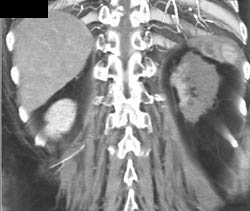

Diagnosis

Complex Cyst Without Tumor